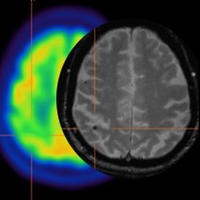

All centres within the Calgary Region involved in fellowship training house state-of-the art imaging infrastructure in all modalities, perform a large number of studies and are involved in both clinical and research endeavors.